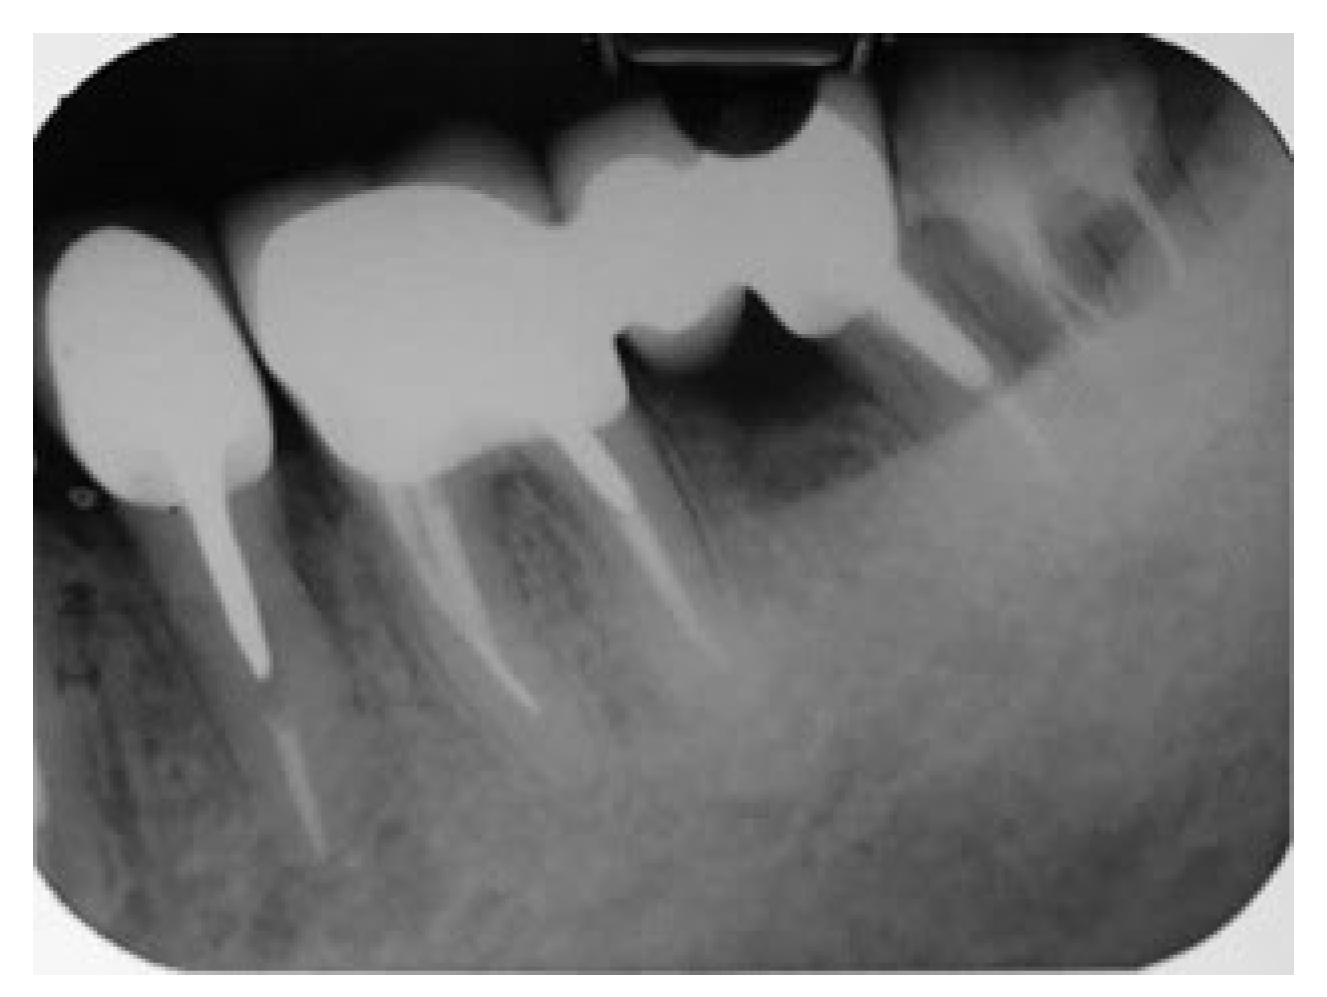

A 55-year-old female patient with no contributory medical history and non-smoker referred by a periodontologist to our clinic for endodontic evaluation and if possible, retreatment of the mesial root of the lower left first molar. According to referring records and as it was indicated in the accompanying periapical radiograph (Figure 15), the initial treatment plan included removal of the distal root of tooth #36. Study of the periapical radiograph showed a furcal involvement in the tooth #36 and a periapical lesion of the untreated distal root. Clinical investigation revealed a type III furcation involvement, first grade mobility combined with deep periodontal pocket in the furcation area while the presence of initial caries was detected at the distal margins of the porcelain fused to metal crown. Based on these findings, removal of the crown was a necessity in order to examine if the tooth crown was restorable. As shown in Figure 16, a periapical radiograph taken after removal of the crown revealed the presence of caries in the disto-buccal part of the tooth and the existence of two distal roots having a furcal involvement in between them.

Figure 15. Initial Periapical X-Ray.

Figure 16. X-ray after crown removal showing the existence of the second distal root.